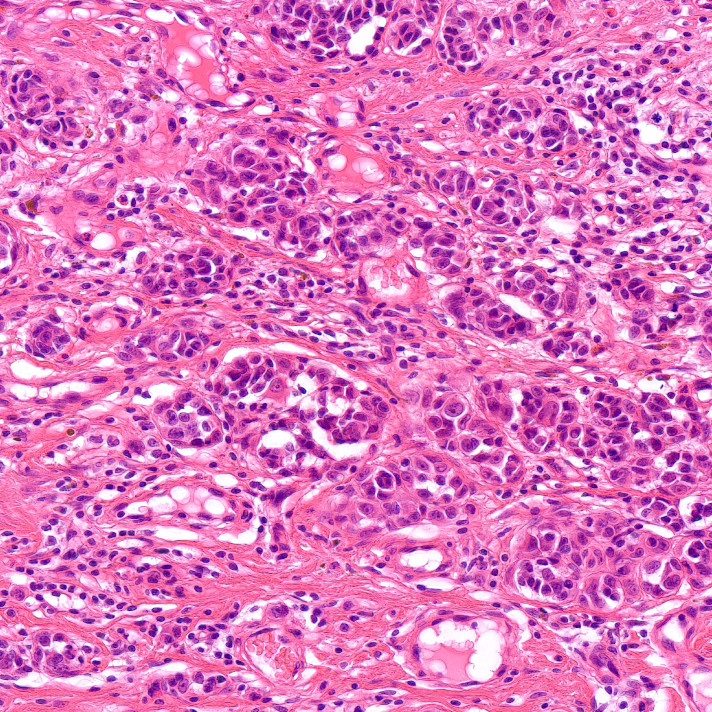

Pathology of transplanted heart rejection using artificial intelligence-based image analysis

Szferle et al. have developed an AI-based pathology workflow to objectively quantify and predict heart transplant rejection from biopsy images…

BIAS supports a wide range of microscope image formats, including brightfield, fluorescent, and pathological images, either directly or through a converter application.